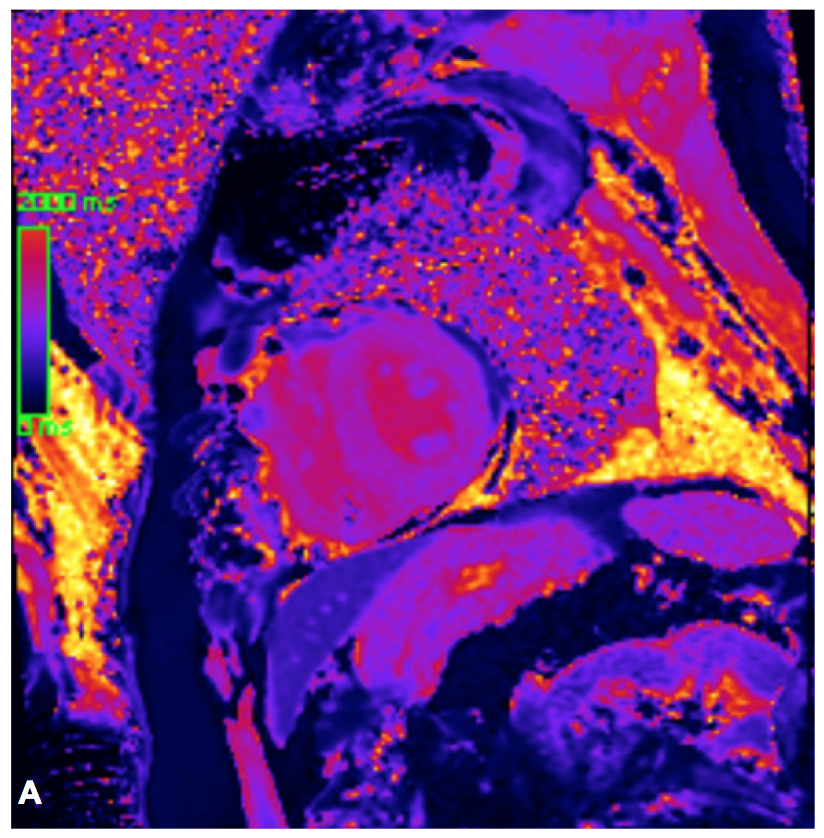

🧲Cardiovascular magnetic resonance for suspected cardiac amyloidosis: where are we now? Mouaz Al-Mallah, M.D MSc Maan Malahfji Yushui Han Ahmed Ibrahim Ahmed, MD MPH Jean Michel Saad #CardioEd #WhyCMR SVCardio Society for Cardiovascular Magnetic Resonance Sociedad Venezolana de Cardiología CardioInfo IANCARDIOLOGY Ariane V. Scarlatelli Macedo

Echocardiography, CMR, and nuclear imaging help diagnose CA & address rapid heart failure. "It Takes a Village: Multimodality Imaging of Cardiac Amyloidosis" by Jean Michel Saad Ahmed Ibrahim Ahmed, MD MPH @DixithaAnugula Yushui Han Mouaz Al-Mallah, M.D MSc & MS Alfawara #DeBakeyCVJournal doi.org/10.14797/mdcvj…